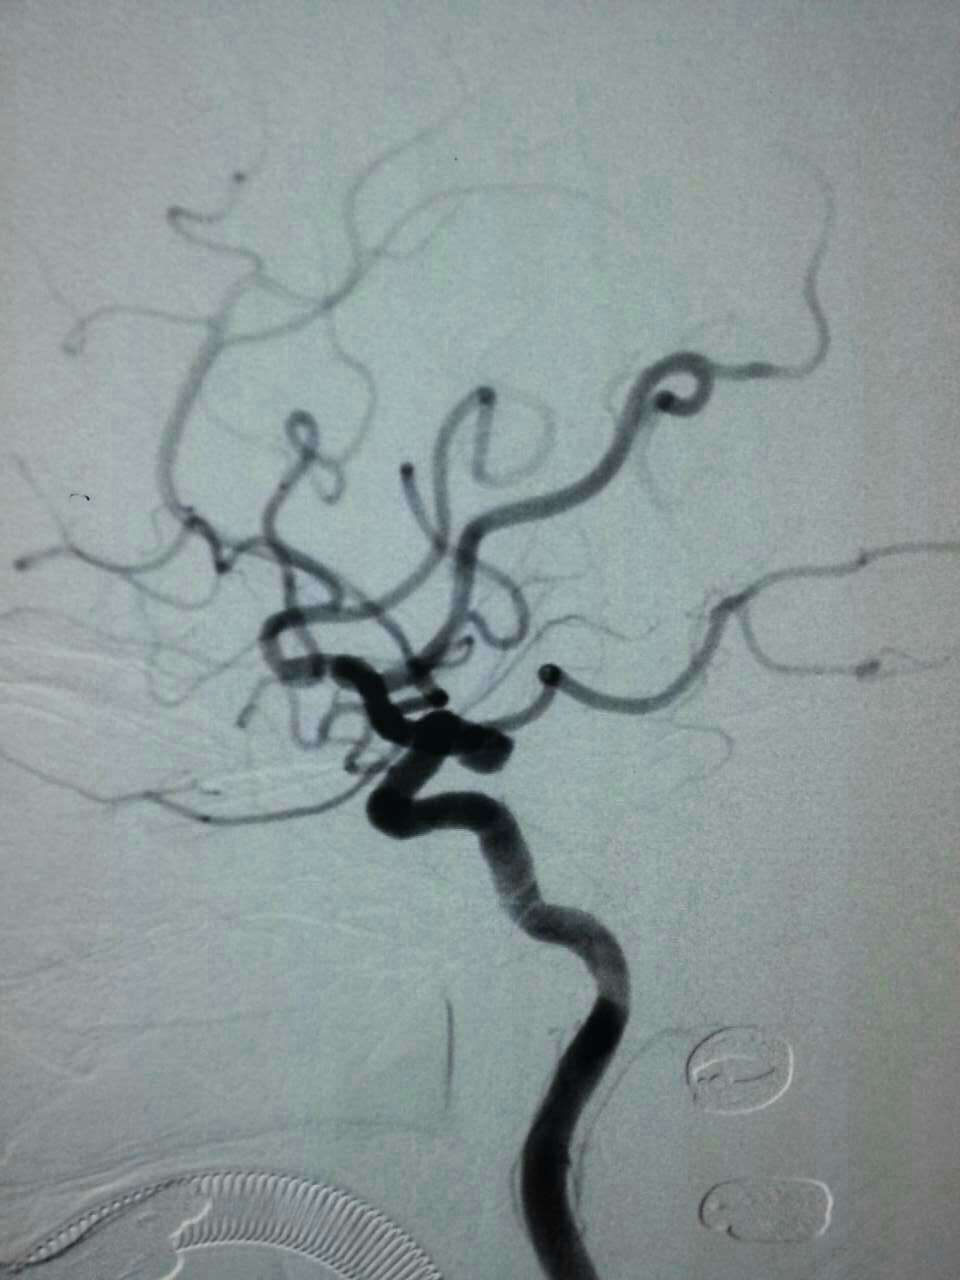

厦门第三医院神经外科每年应用介入栓塞技术抢救颅内动脉瘤破裂患者上百例。昨天晚上,陈金龙副主任医师、何雪阳等技术团队又成功抢救来自同安莲花一位80岁叶女士,大量蛛网膜下腔出血,手术顺利,现患者已清醒,可自行进食。